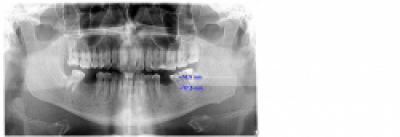

Radiografia dentara este o metoda complementara de investigare a afecțiunilor dento-maxilare, ea reprezentând imaginea dinților si maxilarelor obținuta prin expunerea acestora la radiații X si are ca scop depistarea unor detalii nedetectabile la examenul clinic (leziuni carioase ... Citeste mai departe